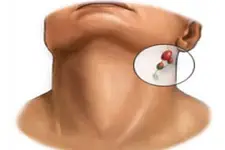

Orta Kulak İltihabı Ameliyatı: Riskleri ve SonrasıOrta kulak iltihabı, tıbbi literatürde otitis media olarak adlandırılan bir durumdur. Bu hastalık, orta kulakta bulunan havalı boşluğun enfeksiyonu ile karakterizedir ve genellikle çocuklarda daha sık görülmektedir. Tedavi sürecinde, ilaç tedavisi yetersiz kaldığında cerrahi müdahale gerekliliği doğabilir. Orta kulak iltihabı ameliyatı, bu enfeksiyonun tedavisinde önemli bir adım olup, beraberinde çeşitli riskler ve sonrasında dikkat edilmesi gereken hususlar barındırmaktadır. Orta Kulak İltihabı Nedir? Orta kulak iltihabı, genellikle viral ya da bakteriyel enfeksiyonlar sonucunda ortaya çıkan bir durumdur. Orta kulak, kulak zarının arkasında yer alan ve ses iletimi için önemli olan bir boşluktur. Bu boşluk, Eustachian tüpü aracılığıyla burun arka kısmına bağlıdır ve bu tüpün tıkanması veya enfeksiyonları, orta kulak iltihabına yol açabilir.

Ameliyat Türleri Orta kulak iltihabı tedavisinde uygulanan başlıca cerrahi yöntemler şunlardır:

Ameliyat Riskleri Her cerrahi müdahale gibi, orta kulak iltihabı ameliyatının da bazı riskleri bulunmaktadır. Bu riskler arasında şunlar yer almaktadır: